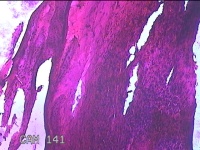

胎盘组织

性别

女

年龄

34岁

临床诊断

头位顺产 胎膜早破

一般病史

停经39+4周,下腹阵痛1小时。

标本名称

大体所见

灰白暗红色胎盘组织19x16x2.3㎝一个,表面光滑,血管突出,颜色发暗,绒毛面结节状,有轻度糜烂,暗红色,有少许凝血块,切面见绒毛内有暗红色血液渗出,边缘蜕膜可见多个小血肿,脐带39x1.5x0.7㎝,螺旋状扭曲,切断脐带,见脐血管内有部分凝血块。